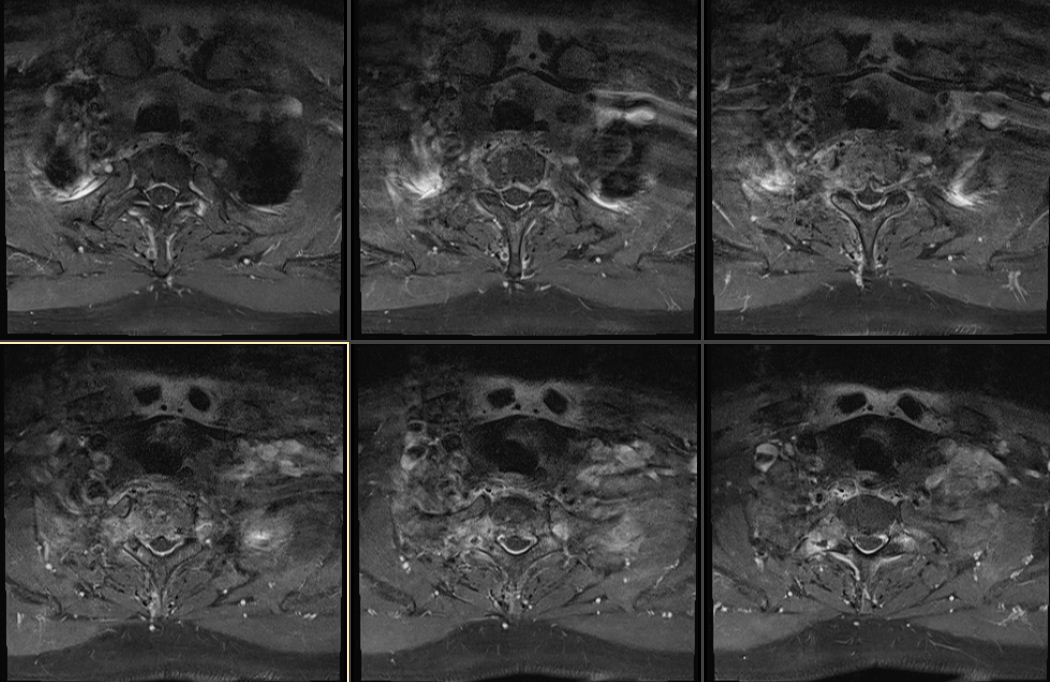

胸椎脊柱转移瘤胸1病例分享

图片尺寸1050x682